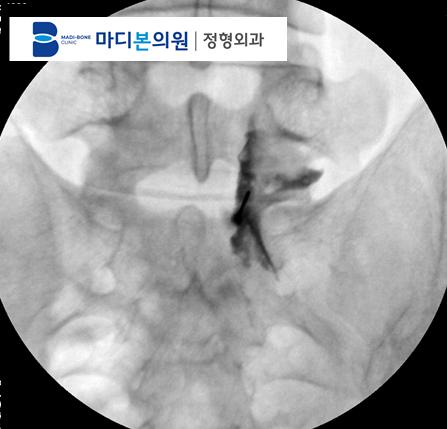

Review: Non-Surgical Outcomes of Disc Herniation

Lumbar Disc Surgery Indications